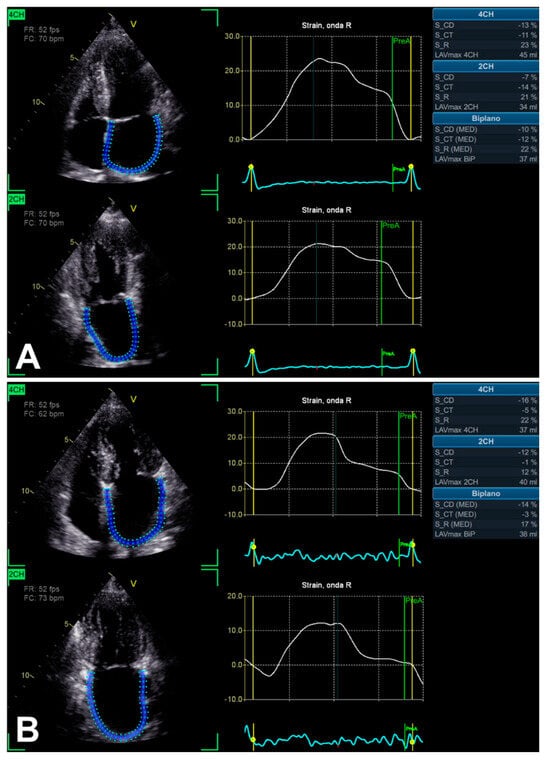

3.2. Left Atrium Strain

| LA strain | 2D apical 4C and 2C views | Probe in apical zone with 4C and 2C views | - Prognostic/predictive value. | - Age and load dependency; - Chest shape dependency; - Image quality-related; - Intervendor and intersoftware variability. |